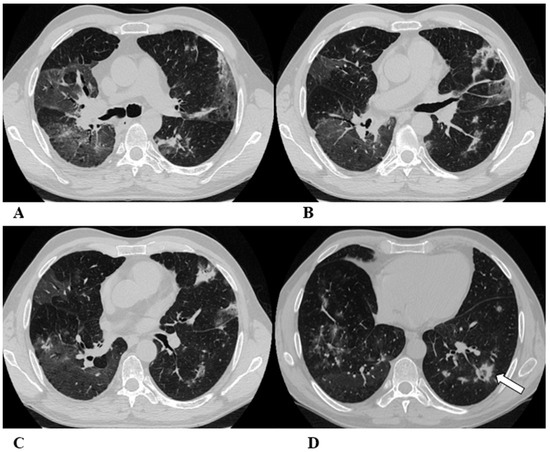

Figure 1.

Organizing pneumonia (OP). Organizing pneumonia is determined by the presence of granulation tissue buds in the alveoli, alveolar ducts and distal bronchioles. On HRCT, OP is characterized by diffuse and bilateral areas of consolidation and ground-glass opacities (GGOs), often migratory, with predominantly peripheral/subpleural and peribronchovascular distribution [9,12]. Other OP findings are the “reversed halo sign” (a focal area of GGO surrounded by a ring of denser air-space consolidation; if the surrounding ring is incomplete, it is mentioned as the “atoll sign” [16]) and, rarely, centrilobular nodules.

(A–D) A 64-year-old man with a diagnosis of small-cell lung cancer with adrenal and brain metastases, treated with nivolumab. Six months after beginning immunotherapy, the patient presented progressive dyspnea and dry cough. Chest auscultation revealed diffuse crackles associated with a moderately restrictive functional pattern. The blood count did not show significant leukocytosis but showed increased inflammatory indexes. The patient benefited from a temporary suspension of immunological therapy with steroid intake, but the subsequent relapse forced a radical change in therapeutic strategy.

Axial chest CT images (A–D) show bilateral confluent areas of GGOs and peripheral and peribronchovascular consolidative opacities.

The structural alteration of the right pulmonary hilum due to the presence of neoplastic tissue, with the infiltration of the ipsilateral main bronchus (A) and the “reversed halo sign” (white arrow (D)), are also visible.